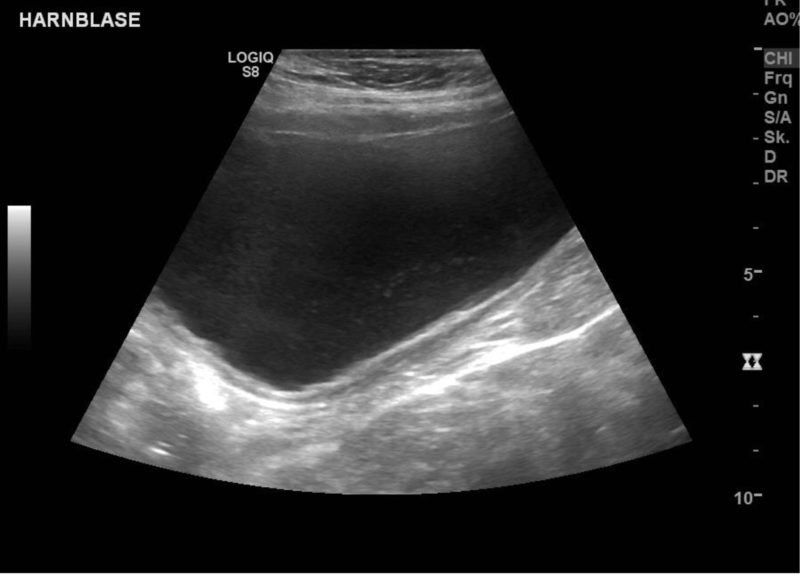

Der Hund kam mit allgemeinen Symptomen wie Unwohlsein/Schwäche, und mit Problemen - verstärktes Trinken und häufiger Harnabsatz, teilweise auch im Haus). In einer unter Ultraschallkontrolle mittels steril entnommener Urinprobe konnten im Sediment bereits mikroskopisch Bakterien nachgewiesen werden. Die Harnblasenwand stellte sich im Ultraschall leicht verdickt (chronisch entzündet) dar.

Die Diagnostik ist immer gleich: Röntgen, Ultraschall und Urinuntersuchung. Bei nur geringer Größe der Steine und je nach Geschlecht und Größe des Hundes ist unter Umständen eine entzündungshemmende, ggf. antibiotische und diäthetische Behandlung möglich.